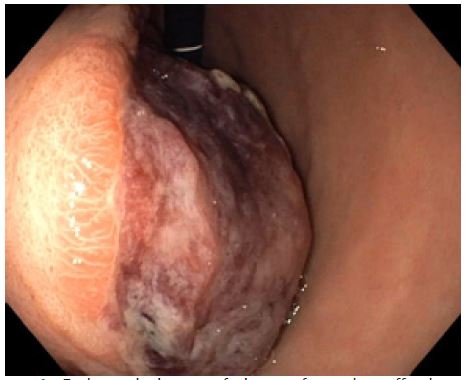

Subsequently, a staging CT scan with iodinated contrast medium confirmed the presence of the large stomach neoformation (9.5 cm in diameter) with an exophytic development (Figure 2). It was suspected to be a GIST and was in contact with the left hepatic lobe, the intra-abdominal wall, the pancreas, and the duodenum, without any lymphadenopathies or signs of possible metastasis (Figure 2).

Figure 2: Contrast-enhanced abdomen Computed Tomography (CT) showing the stomach neoformation.